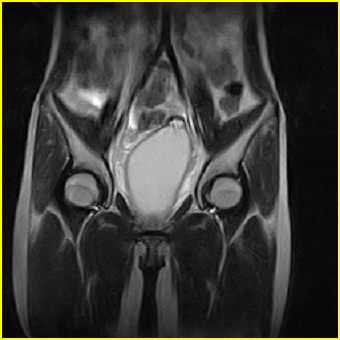

女、15岁、下腹疼痛2天,排尿困难1天。查体:处女膜闭锁,距处女膜约4至5cm处扪及一约5cm直径的圆形包块,张力较高,触痛明显、欠活动。b超提示子宫增大伴宫内增强回声团。

影像意见:子宫直肠陷凹积血。

更正影像意见:阴道积血。

处女膜闭锁,阴道积血

处女膜闭锁,阴道积血,子宫积血.

先天性处女膜闭锁,伴阴道积血,不除外先天性阴道粘液囊肿形成。

阴道积血,子宫积血.

子宫及阴道积血。

处女膜闭锁,伴子宫及阴道积血.